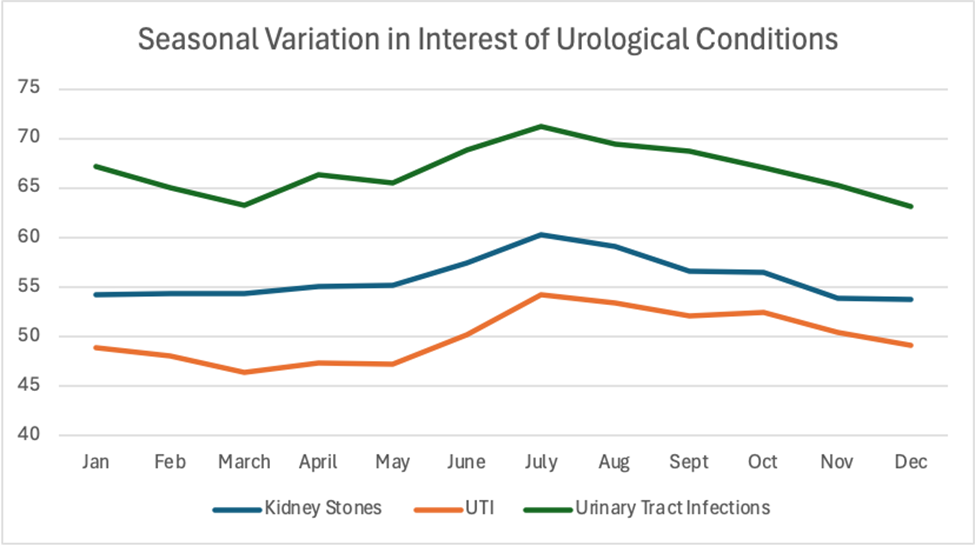

Seasonal Variation of Public Interest in Urinary Tract Infections and Kidney Stones: A Google Trends Analysis

Background: Kidney stones and urinary tract infections (UTIs) are two of the most common urologic conditions, both of which have...Read More